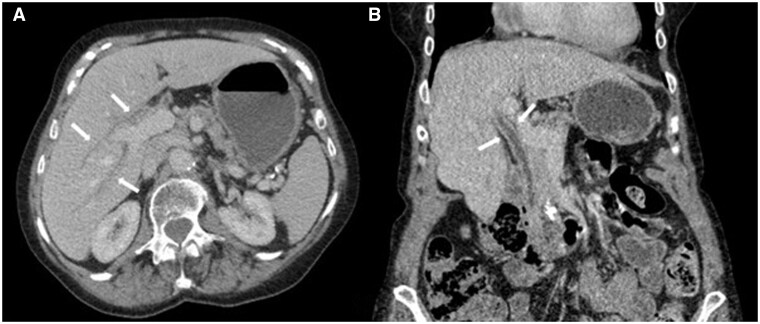

This case study describes a female patient in her late 70s who developed autoimmune cholangitis a year after finishing 35 cycles of pembrolizumab for the treatment of her non-small cell lung cancer. The diagnosis was initially missed and delayed; the patient's agoraphobia and the COVID-19 pandemic were noted as contributing factors.